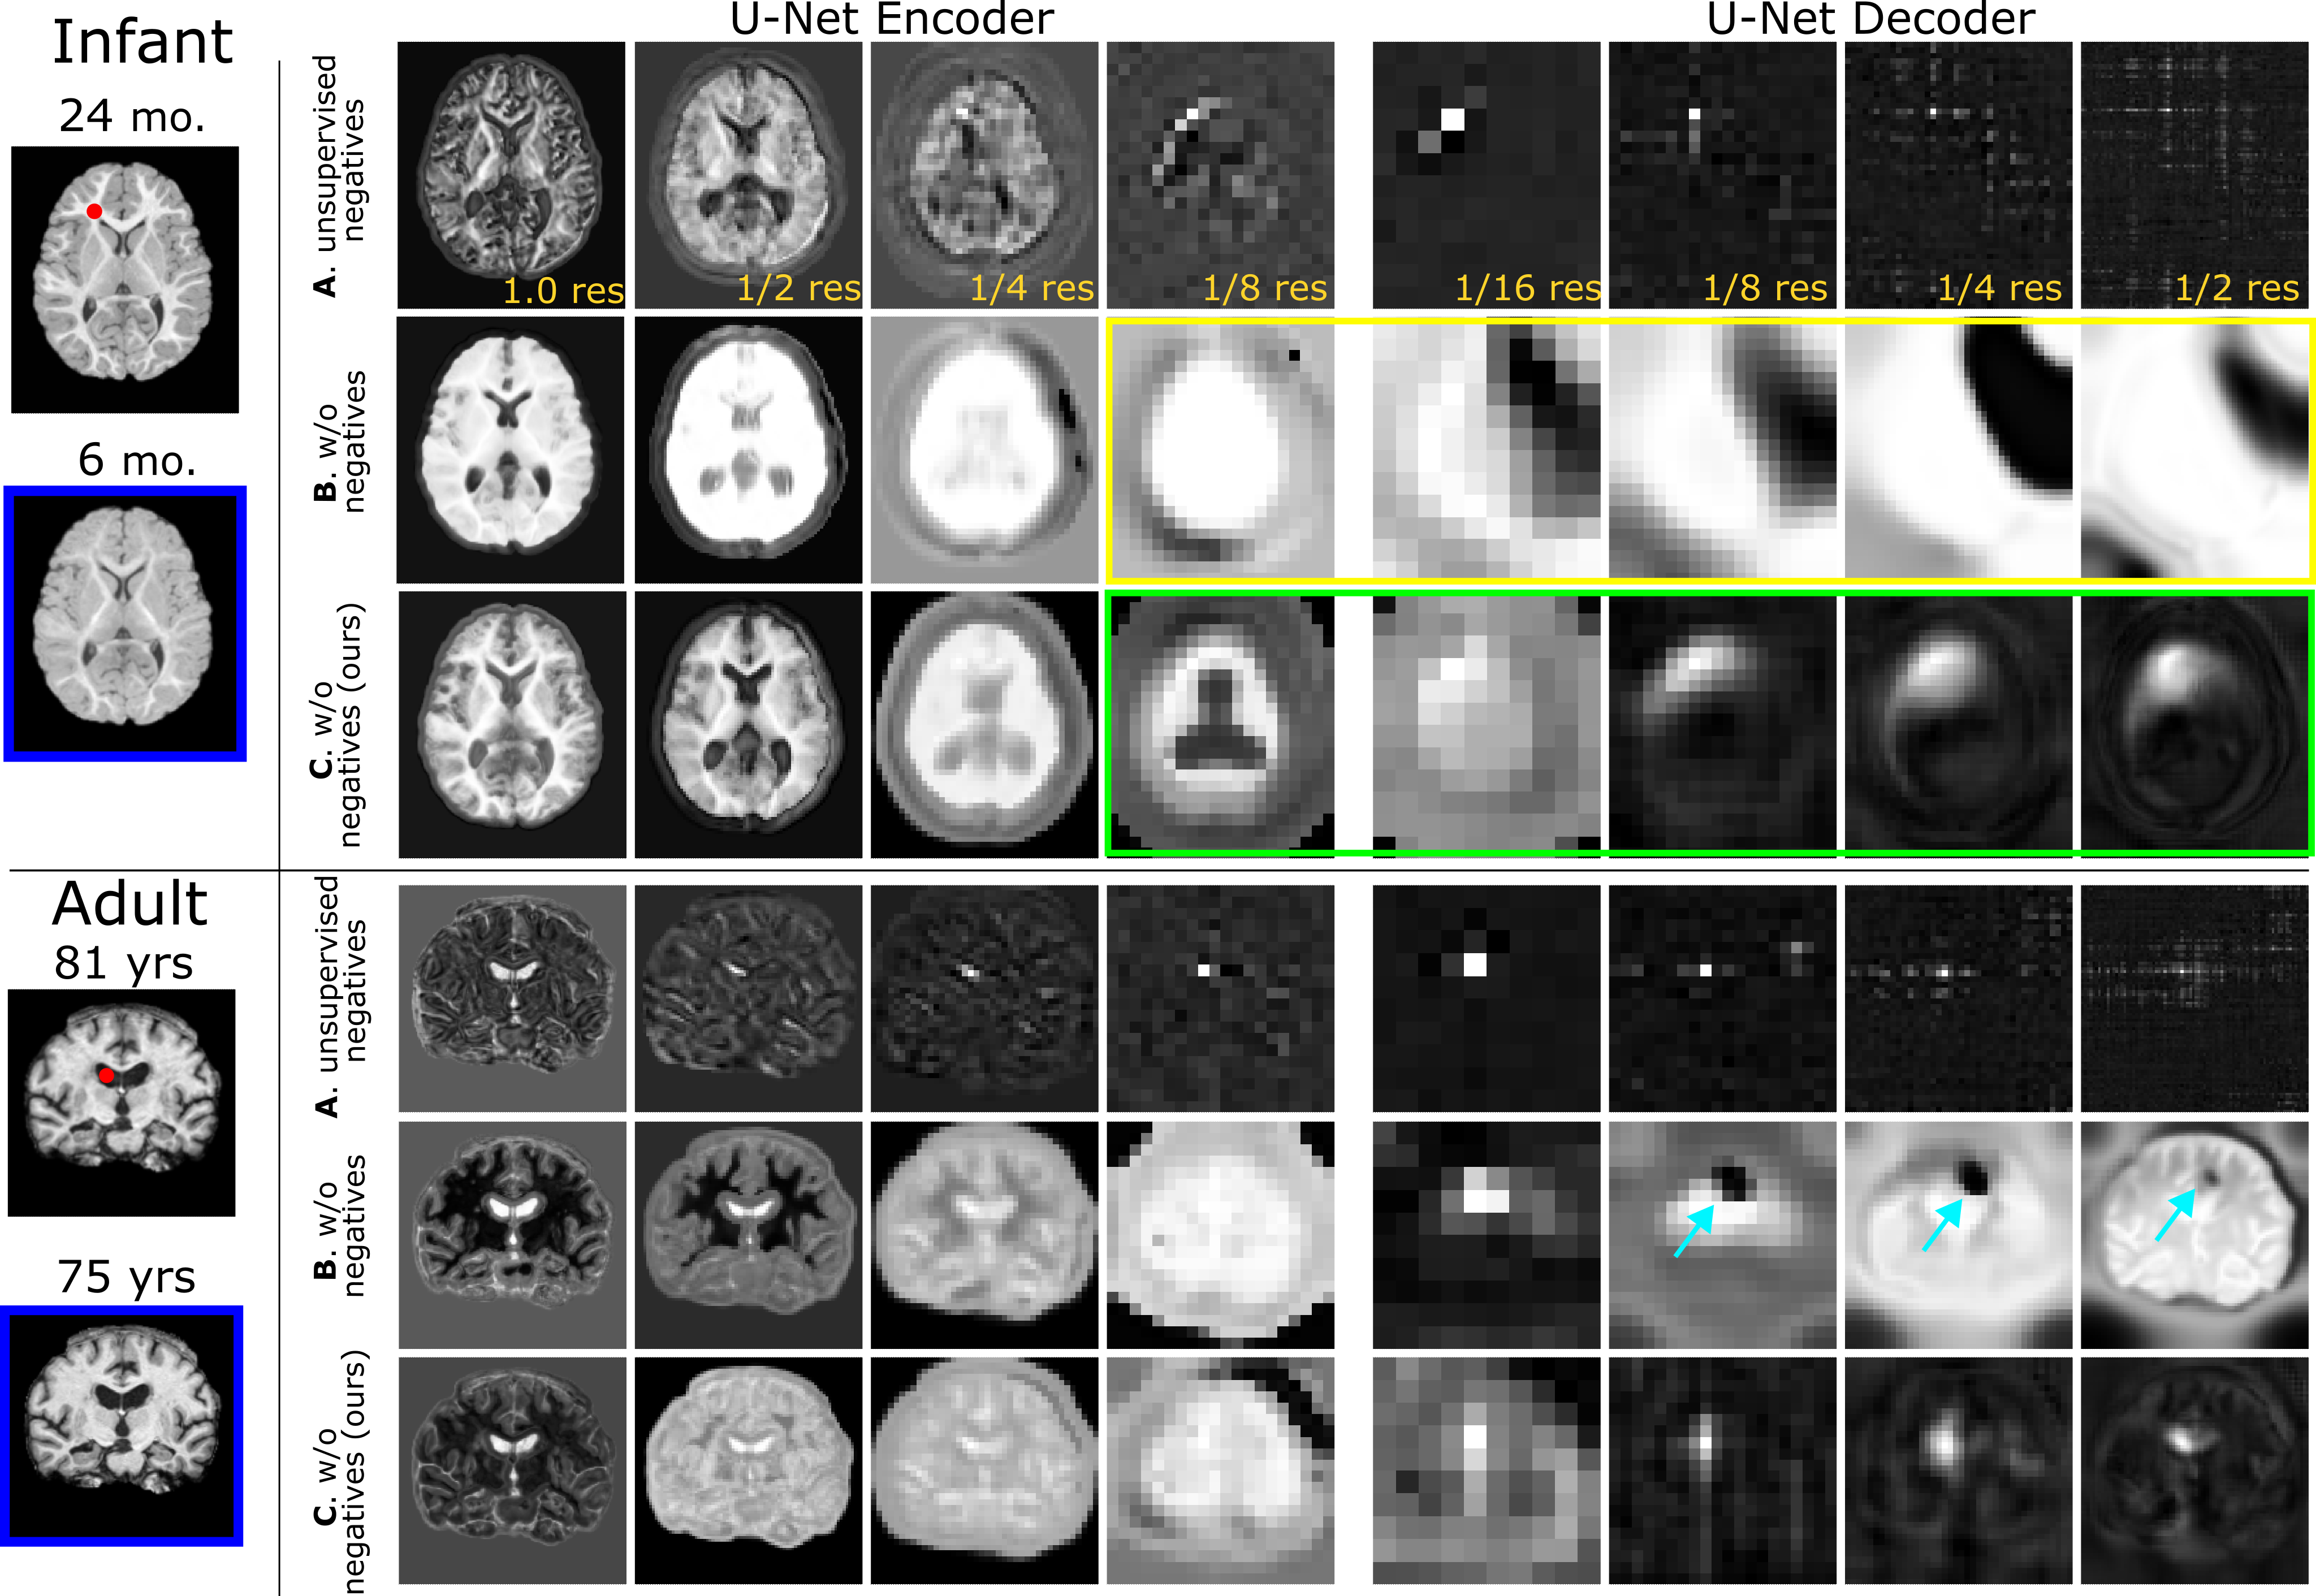

Recent self-supervised advances in medical computer vision exploit global and local anatomical self-similarity for pretraining prior to downstream tasks such as segmentation. However, current methods assume i.i.d. image acquisition, which is invalid in clinical study designs where follow-up longitudinal scans track subject-specific temporal changes. Further, existing self-supervised methods for medically-relevant image-to-image architectures exploit only spatial or temporal self-similarity and only do so via a loss applied at a single image-scale, with naive multi-scale spatiotemporal extensions collapsing to degenerate solutions. To these ends, this paper makes two contributions: (1) It presents a local and multi-scale spatiotemporal representation learning method for image-to-image architectures trained on longitudinal images. It exploits the spatiotemporal self-similarity of learned multi-scale intra-subject features for pretraining and develops several feature-wise regularizations that avoid collapsed identity representations; (2) During finetuning, it proposes a surprisingly simple self-supervised segmentation consistency regularization to exploit intra-subject correlation. Benchmarked in the one-shot segmentation setting, the proposed framework outperforms both well-tuned randomly-initialized baselines and current self-supervised techniques designed for both i.i.d. and longitudinal datasets. These improvements are demonstrated across both longitudinal neurodegenerative adult MRI and developing infant brain MRI and yield both higher performance and longitudinal consistency.